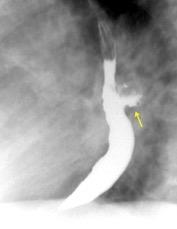

Mounier-Kuhn

Fibrosis del lóbulo superior (Tb, Sarcoidosis) Neumonitis de hipersensibilidad Espondilitis anquilopoyéytica Ehlers-Danlos

Traqueobroncomegalia de Mounier-Kuhn con neumonía del LID

Wegner F. CT of Mounier -Kuhn Disease. Radiology 2020

Traqueobroncomegalia de Mounier-Kuhn

Dilatación marcada de tráquea y grandes bronquios.

Traqueobroncomalacia 67% + Protrusión del tejido músculo-membranoso redundante entre los anillos cartilaginosos.(diverticulosis traqueal)

Infección respiratoria recurrente (88%)

Debilidad del aparato muco -ciliar Fumadores.

Schmitt P et al. Respiratory Conditions Associated with Tracheobronchomegaly (Mounier-Kuhn Syndrome): A Study of Seventeen Cases. Respiration 2016

Wegner F. CT of Mounier-Kuhn Disease. Radiology 2020